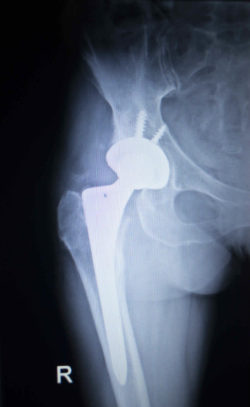

The Pinnacle hip replacement system is a metal-on-metal implant system made from titanium and cobalt. The implant system reportedly uses “TruGlide technology”, allowing the body to form lubrication between surfaces which “enhances performance with smooth, natural motion and less friction.”

The DePuy Pinnacle hip implant lawsuit claims that the replacement system is defective due to the release of metal debris. Regular wear allegedly results in metallic ions in the blood which can cause serious complications.

“Implantation of the Pinnacle Hip results in the nearly immediate systemic release of high levels of toxic metal cobalt-chromium ions into every hip implant patient’s tissue and bloodstream,” the DePuy Pinnacle hip implant lawsuit states. “This is because cobalt-chromium metal particles are released by friction from the metal femoral head rotating within the metal liner.”